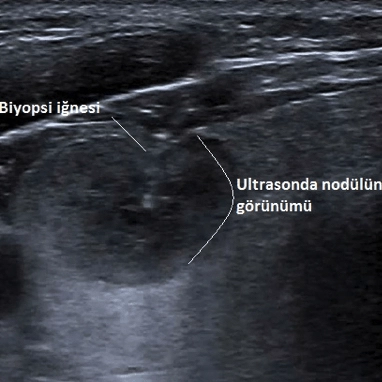

Tiroid İnce İğne Aspirasyon Biyopsisi (TİİAB)

Genellikle adı nedeniyle korkulan ancak uygulaması kolay ve riski son derece düşük olan bir işlemdir. Bir santim civarındaki nodüllere biyopsi yapmak, tüm dünyada kabul gören bir kuraldır. Hastaya cerrahi tedavi düşünülse bile cerraha, operasyon sırasında yol göstermesi açısından biyopsi yapılması uygun olur. Çok ağrılı bir işlem olmadığı için çoğunlukla anestezi uygulamak gerekmez.